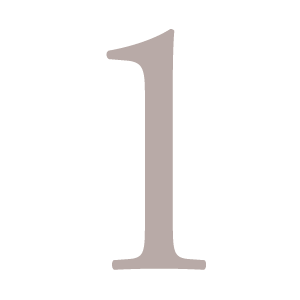

インプラント体は

人工の歯の根

インプラントそのものはチタンで出来ています。歯の根と同じように約10mm程度の長さをしているチタン製の人工物が、歯の根の代わりにあごの骨に埋め込まれます。

WHATS.02

インプラント体は

骨と結合して安定

インプラント体の素材であるチタンには、時間の経過とともに骨と一体化して固まってしまう性質があり、この作用を利用して、人工の歯の根をしっかりと固定させています。インプラントはネジの様な形状で溝が刻まれており、スクリューさせてあごの骨にしっかりと埋め込めるようになっています。またインプラントのメーカーごとに、より良く骨と結合させるために工夫が凝らされた表面形状で作製されており、これがメーカーごとの大きな性能の違いとなっています。